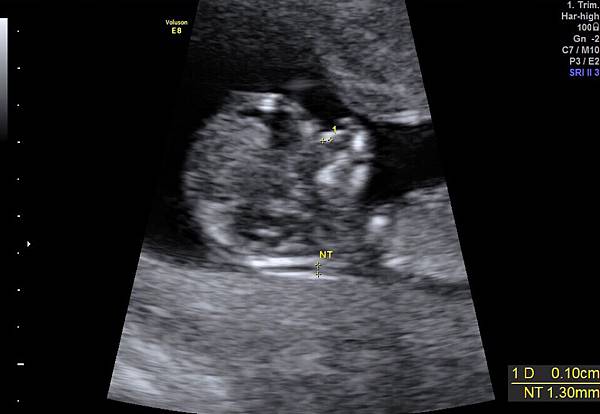

12/22 初期唐氏症篩檢+子癲前症風險

原本想說等去了「禾馨」後,在決定第一次的產檢的項目等要在哪裡檢查,殊不知禮拜一去「李木生」後,護士就先幫我約了今天做初唐篩檢;但其實原本今天要檢查什麼我是不知道的,我一直以為是要來看抽血報告之類的,到了婦產科才知道是要做初唐篩檢。所以既然都來了,就先檢查吧!台北市政府好像有補助檢查費用給台北市民,所以今天我只需要在付差額$800(但他們沒有解說原本的費用是多少,補助是多少)。

今天的檢查還好不需要排隊,不讓禮拜六門診的人數真的不是開玩笑的。在填寫完基本資料後,就開始掃超音波,超音波技師非常的安靜,沒有多做講解,我問說「請問是等一下醫生會在講解嗎?」,他回說他先確認寶寶位置在解說。開始解說的時候,是有解說,但是是非常快速的帶過,有看到鼻骨、透明頸的高度、手、腳、頭骨等,但是都是點到就跳過,所以我一時有點無法吸收技師快速的解說,幾乎馬上就忘記。還好照完後,影像會直接傳送到木生APP,我可以慢慢看;基本上就是「正常」。除了初唐的抽血項目外,有在加做子癲前症抽血檢查,但NIFTY+還在考慮中,所以沒有一起抽(如果2項一起抽會有優惠,原價$27200,優惠$26200)。但回家跟家人討論及上網做了些功課後,還是決定會回去補抽做NIFTY+。

附上檢查後的幾張影像,和一張外星人的3D照。